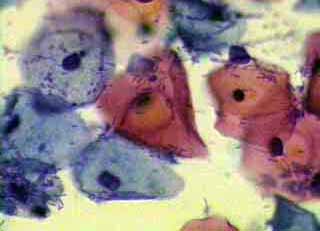

Ιατρικές Εικόνές - κυτταρολογικών επιχρισμάτων κατά Papanicoloau και η συσχέτιση τους με το ιστορικό

Το ενδιαφέρον του κλινικού γυναικολόγου στο πόρισμα του κυτταρολογικού επιχρίσματος του τραχήλου της μήτρας, περιορίζεται συνήθως στο συμπέρασμα του, σχετικά με την ύπαρξη κάποιας δυσπλασίας ή έστω φλεγμονής, στην περιοχή.

Ωστόσο ακόμη και το λεγόμενο ‘’φυσιολογικό’’ επίχρισμα, μπορεί να μας δώσει μία επί πλέον αξιόλογη πληροφόρηση, αν τα ευρήματα του ενταχθούν σωστά από τον κλινικό γιατρό, τόσο στην χρονική συγκυρία, όσο και στο ιστορικό, ή στα κλινικά, κολποσκοπικά και υπερηχογραφικά ευρήματα.

Η γενικότερη γυναικολογική οπτική γωνία, στην ερμηνεία ενός κυτταρολογικού πορίσματος, είναι αρκετά σημαντική για την αξιολόγηση άλλων προβλημάτων, πέραν των δυσπλασιών.

Οι εικόνες και τα πορίσματα που επιδεικνύονται, είναι τυχαία ευρήματα ενός απογευματινού ιατρείου.